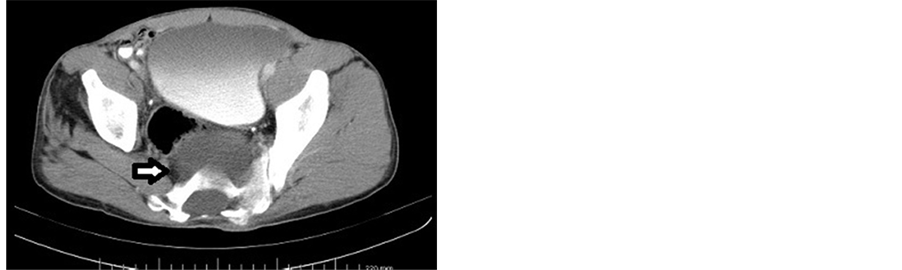

A 33-year-old man applied to our hospital with the complaints of a long-lasting constipation and a nonspecific lower abdominal pain. His physicals did not reveal any abnormalities, and his routine laboratory work-up was within normal limits. The patient was examined by ultrasonography (US) (DC-7, Mindray Ltd., China). US examination disclosed a cystic mass of a size of 6.0 × 7.5 × 7.5 cm, at the posterior aspect of the bladder. The lesion was extending to the presacral space posteriorly, and had a bilobulated appearance at this site (Figure 1). No solid components could be visualized in the cyst. Although an ASM was among the differential list, a Computed Tomography (CT) examination was planned because other differential diagnostic possibilities could not yet be ruled out at this level of the evaluation. CT examination was performed with a 16-row multidetector scanner (Somatom Sensation 16, Siemens AG, Germany). CT revealed a bony defect at the anterior part of the sacral bone, together with a presacral cystic mass which demonstrated a connection with the dural sac (Figure 2). Magnetic Resonance Imaging (MRI) examination was done in a 1.5 Tesla (T) MRI system (Magnetom, Siemens AG, Germany). At MRI, a cystic mass which was hypointense on T1-weighted (T1W), and hyperintense on T2-weighted (T2W) sequences at the presacral space was demonstrated. Sagittal images clearly demonstrated that the cyst was in connection with the dural sac through the bony defect at the sacrum (Figure 3). It was also noted that the spinal cord was low-lying and ending at the level of the lower plate of the L5 vertebral body (Fig- ure 4). After intravenous contrast injection, no solid or neural components could be visualized in the mass. The axial T1W images showed that the mass was exerting pressure on the rectum (Figure 5). An anteroposterior (AP) pelvis radiogram demonstrated a sacral deformity and the scimitar sign (Figure 6). Upon these imaging findings, the patient got the diagnosis of an anterior sacral meningocele. The neurologic examination of the patient revealed no deficits. The patient was provided satisfying information concerning the necessity of surgery and follow-up. But, rejecting the idea of surgery, the patient, who demonstrated no clinical symptoms other than constipation, was put into a follow-up program. The patient was followed by US for a year, and no progression in the lesion size was detected during this time period.

Figure 2. At axial CT, hypodense pelvic mass lesion is seen extending to the retroperitoneal space through a bony defect at the anterior wall of the sacrum (arrow).

Conventional radiography, US, CT and MRI all play important roles in the diagnosis of ASM. Radiologic imaging findings include a bony defect at the anterior wall of the sacrum, enlarged foramens, and a cystic mass localized at the pelvis. The relation and continuation of the pelvic cyst and the dural sac must be demonstrated in order to reach a definitive diagnosis.

The pelvic cystic mass is easily demonstrated at US. But in order to make a definitive diagnosis, the relation of the mass with the dural sac must be disclosed well. Especially those cysts with narrow necks may be mistaken for an ovarian cyst or a full bladder [2] [4] [14] . It is very important to make a definitive differential diagnosis of an ASM in pelvic cystic masses. This is because in patients who suffer from this disease and who lack this differential evaluation, a surgical or an interventional approach may lead to very serious complications such as a meningitis or a sudden fall in intracranial pressure [6] [9] [15] . US is also very valuable in the follow-up of patients who are not scheduled for surgery [4] . CT may demonstrate the bony abnormalities at the anterior sacral wall in a much better fashion than any other imaging modality. Administration of intrathecal contrast media may disclose the relation of the dural sac and the presacral cyst perfectly. It may also help detect any solid components of the cystic mass [4] . But since CT myelography is an invasive procedure and utilizes ionizing radiation, it must be saved for those cases with cysts with a narrow neck which present difficulties in the detection of the relation of the cyst and the thecal sac [12] .